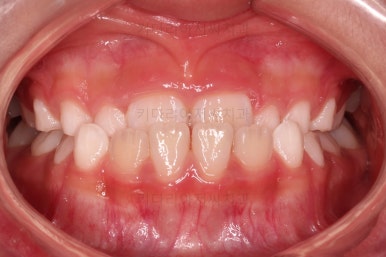

치료 4개월째인데요.

열심히 모범적으로 잘 사용해 주었고, 앞니가 아슬아슬하게 앞니끼리 맞물리는 상태까지 개선이 되었네요.